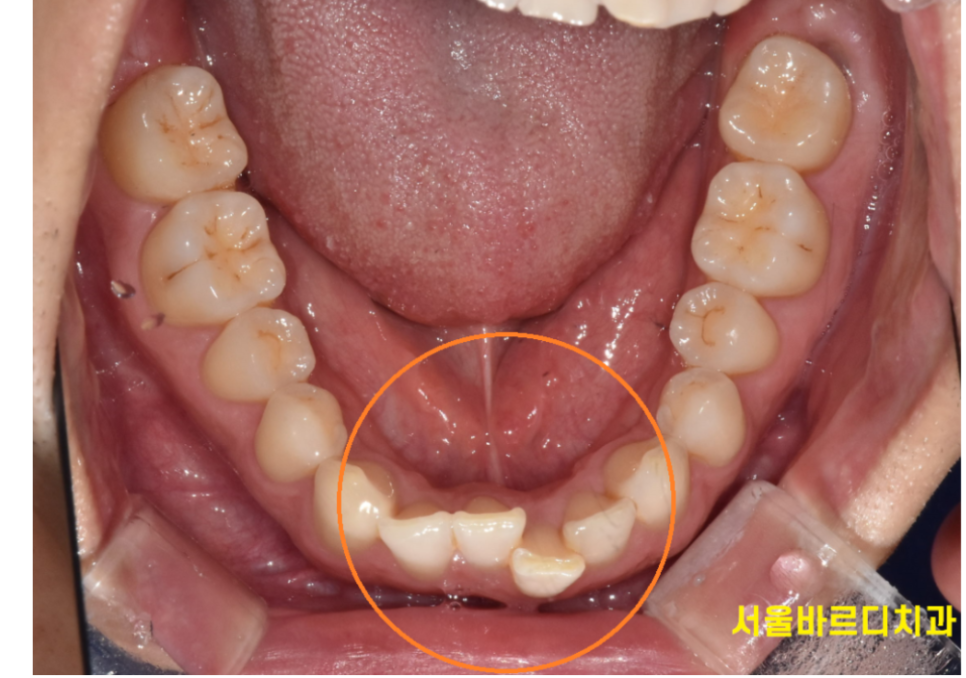

- 충치나 잇몸 질환이 자주 발생하는 경우

덧니나 치아가 겹쳐 있는 경우 칫솔질이 제대로 되지 않아

충치나 잇몸 질환이 발생할 확률이 높아집니다.

특히 아래 앞니가 모여있는 경우...

잇몸질환으로 추후 치아가 흔들리는 경우를 많이 보았습니다.